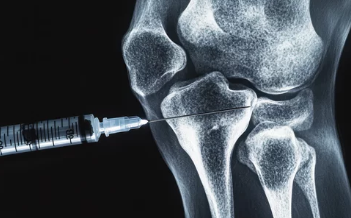

(1) 약물 치료

- 급성 발작 치료: 비스테로이드성 소염진통제(NSAIDs), 콜히친(Colchicine), 스테로이드 주사를 통해 염증과 통증을 완화합니다.

- 요산 저하제: 알로푸리놀(Allopurinol), 페북소스타트(Febuxostat) 등은 요산 수치를 낮추는 데 사용됩니다.

- 통풍 예방 약물: 반복적인 발작 예방을 위해 장기적으로 약물을 복용할 수 있습니다.